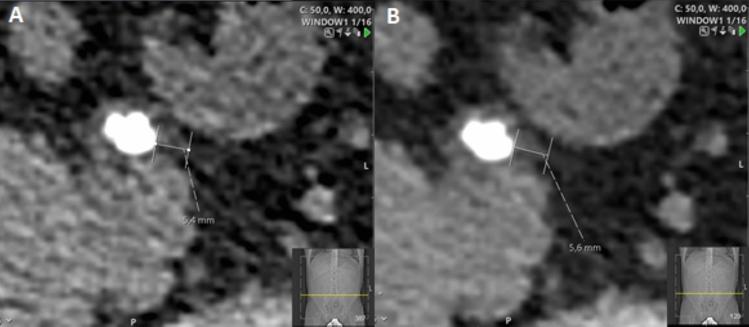

Stone size and location are key factors in predicting spontaneous stone passage (SSP), but little attention has been paid to the influence of radiological signs of stone impaction (RSSI). This research aims to determine whether RSSI, alongside stone size, can predict SSP and to evaluate the consistency of ureteral wall thickness (UWT) measurements among observers. In this retrospective study, 160 patients with a single upper or middle ureteral stone on acute non-enhanced computed tomography (NCCT) were analysed. Patient data were collected from medical records. Measurements of RSSI, including UWT, ureteral diameters, and average attenuation above and below the stone, were taken on NCCT by four independent readers blind to the outcomes. The cohort consisted of 70% males with an average age of 51 ± 15. SSP occurred in 61% of patients over 20 weeks. The median stone length was 5.7 mm (IQR: 4.5-7.3) and was significantly shorter in patients who passed their stones at short- (4.6 vs. 7.1, p < 0.001) and long-term (4.8 vs. 7.1, p < 0.001) follow-up. For stone length, the area under the receiver operating characteristic curve (AUC) for predicting SSP was 0.90 (CI 0.84-0.96) and only increased to 0.91 (CI 0.85-0.95) when adding ureteral diameters and UWT. Ureteral attenuation did not predict SSP (AUC < 0.5). Interobserver variability for UWT was moderate, with ± 2.0 mm multi-reader limits of agreement (LOA). The results suggest that RSSI do not enhance the predictive value of stone size for SSP. UWT measurements exhibit moderate reliability with significant interobserver variability.

结石大小和位置是预测结石自行排出(SSP)的关键因素,但很少关注结石嵌顿的放射学征象(RSSI)的影响。本研究旨在确定 RSSI 与结石大小是否可以预测 SSP,并评估观察者之间输尿管壁厚度(UWT)测量的一致性。在这项回顾性研究中,对 160 名在急性非增强计算机断层扫描(NCCT)上有单个上或中输尿管结石的患者进行了分析。患者数据从病历中收集。由四位独立的读者在 NCCT 上进行 RSSI 测量,包括 UWT、输尿管直径以及结石上下的平均衰减,读者对结果不知情。队列由 70%的男性组成,平均年龄为 51±15 岁。20 周内 61%的患者出现 SSP。结石长度的中位数为 5.7mm(IQR:4.5-7.3),在短期(4.6 与 7.1,p<0.001)和长期(4.8 与 7.1,p<0.001)随访中排出结石的患者中明显更短。对于结石长度,预测 SSP 的受试者工作特征曲线(ROC)下面积(AUC)为 0.90(CI 0.84-0.96),仅当加入输尿管直径和 UWT 时,AUC 才增加到 0.91(CI 0.85-0.95)。输尿管衰减不能预测 SSP(AUC<0.5)。UWT 的观察者间变异性为中度,多读者的±2.0mm 一致性限(LOA)。结果表明,RSSI 不会增强结石大小对 SSP 的预测价值。UWT 测量具有中度可靠性,观察者间存在显著的变异性。